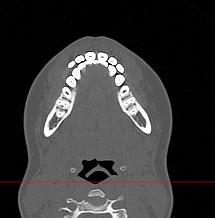

Мультиспиральная компьютерная томография челюстно-лицевой области относится к лучевым методам исследования и включает в себя сканирование верхней и нижней челюстей, зубов, височно-нижнечелюстных суставов, мягкотканных структур ротовой полости. Преимуществами КТ является быстрота, безболезненность и неинвазивность (то есть исследование не требует вмешательства в организм).

В результате сканирования получается серия изображений, которые отображают состояние челюстно-лицевой зоны, особенности анатомического строения и позволяют выявить воспалительные изменения, травматические повреждения, опухолевые образования, аномалии развития. Проявления артроза височно-нижнечелюстных суставов могут создавать неприятные ощущения при жевании. Также зачастую воспалительные изменения придаточных пазух носа связаны с пролабированием зубов верхней челюсти в область альвеолярных бухт верхнечелюстных синусов.

В наших медицинских центрах обследование челюстно-лицевой зоны проводится на современных мультиспиральных компьютерных томографах экспертного класса TOSHIBA AQUILION. 64- и 128-срезовый компьютерные томографы послойно сканируют исследуемую область с шагом от 0,5 мм, получая детальные изображения высокого уровня четкости и контрастности.

С помощью цифровой обработки данных проводится объемная реконструкция и построение 3D-изображений челюстно-лицевой области, что дает возможность визуализировать пространственное соотношение анатомических структур и повышает точность диагностики. При этом возможности аппаратов обеспечивают пониженный уровень дозы облучения для организма человека.